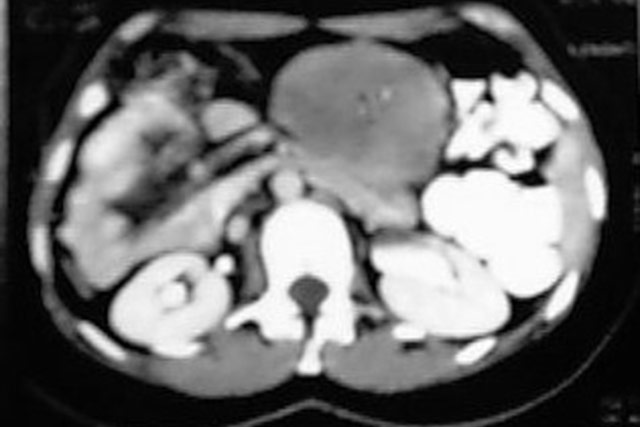

Fibrosarcoma de Mesentério